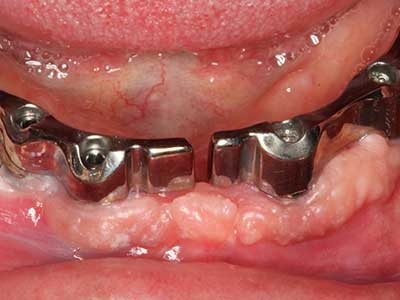

Si es preciso realizar intervenciones quirúrgicas en las que el hueso está en contacto directo con estructuras sensibles, como son los vasos sanguíneos o los nervios, los instrumentos rotativos presentan un enorme potencial de provocar lesiones iatrogénicas. Así, precisamente en la representación de nervios después de una lesión iatrogénica, o en el transcurso de la lateralización de un nervio para resecciones, reconstrucciones o incorporación de implantes, los equipos piezoeléctricos pueden resultar muy útiles para preparar la tapa ósea y retirar las partes de tejido duro cercanas al nervio (fig. 17-20). Por lo general, un ligero contacto del cordón nervioso con el inserto piezoeléctrico no tiene consecuencia alguna; ahora bien, un procedimiento poco cuidadoso con movimientos tipo sierra o piezas de trabajo sobre la base ósea aún existente puede provocar lesiones nerviosas temporales o incluso permanentes. Con todo, el riesgo de sufrir una lesión de este tipo se considera significativamente inferior que en los casos en los que se utilizan sierras y fresas (Pereira, Gealh et al. 2014).